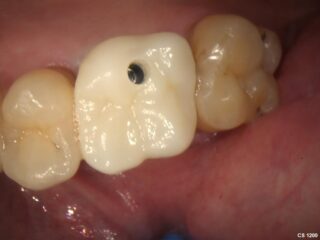

Once the implant is fully healed, a custom-made crown is placed on top. This crown looks and functions like a natural tooth, restoring your smile and bite.

Once healing is complete, a custom-made dental crown is fitted onto the implant. This restores both the function and natural look of the missing tooth.